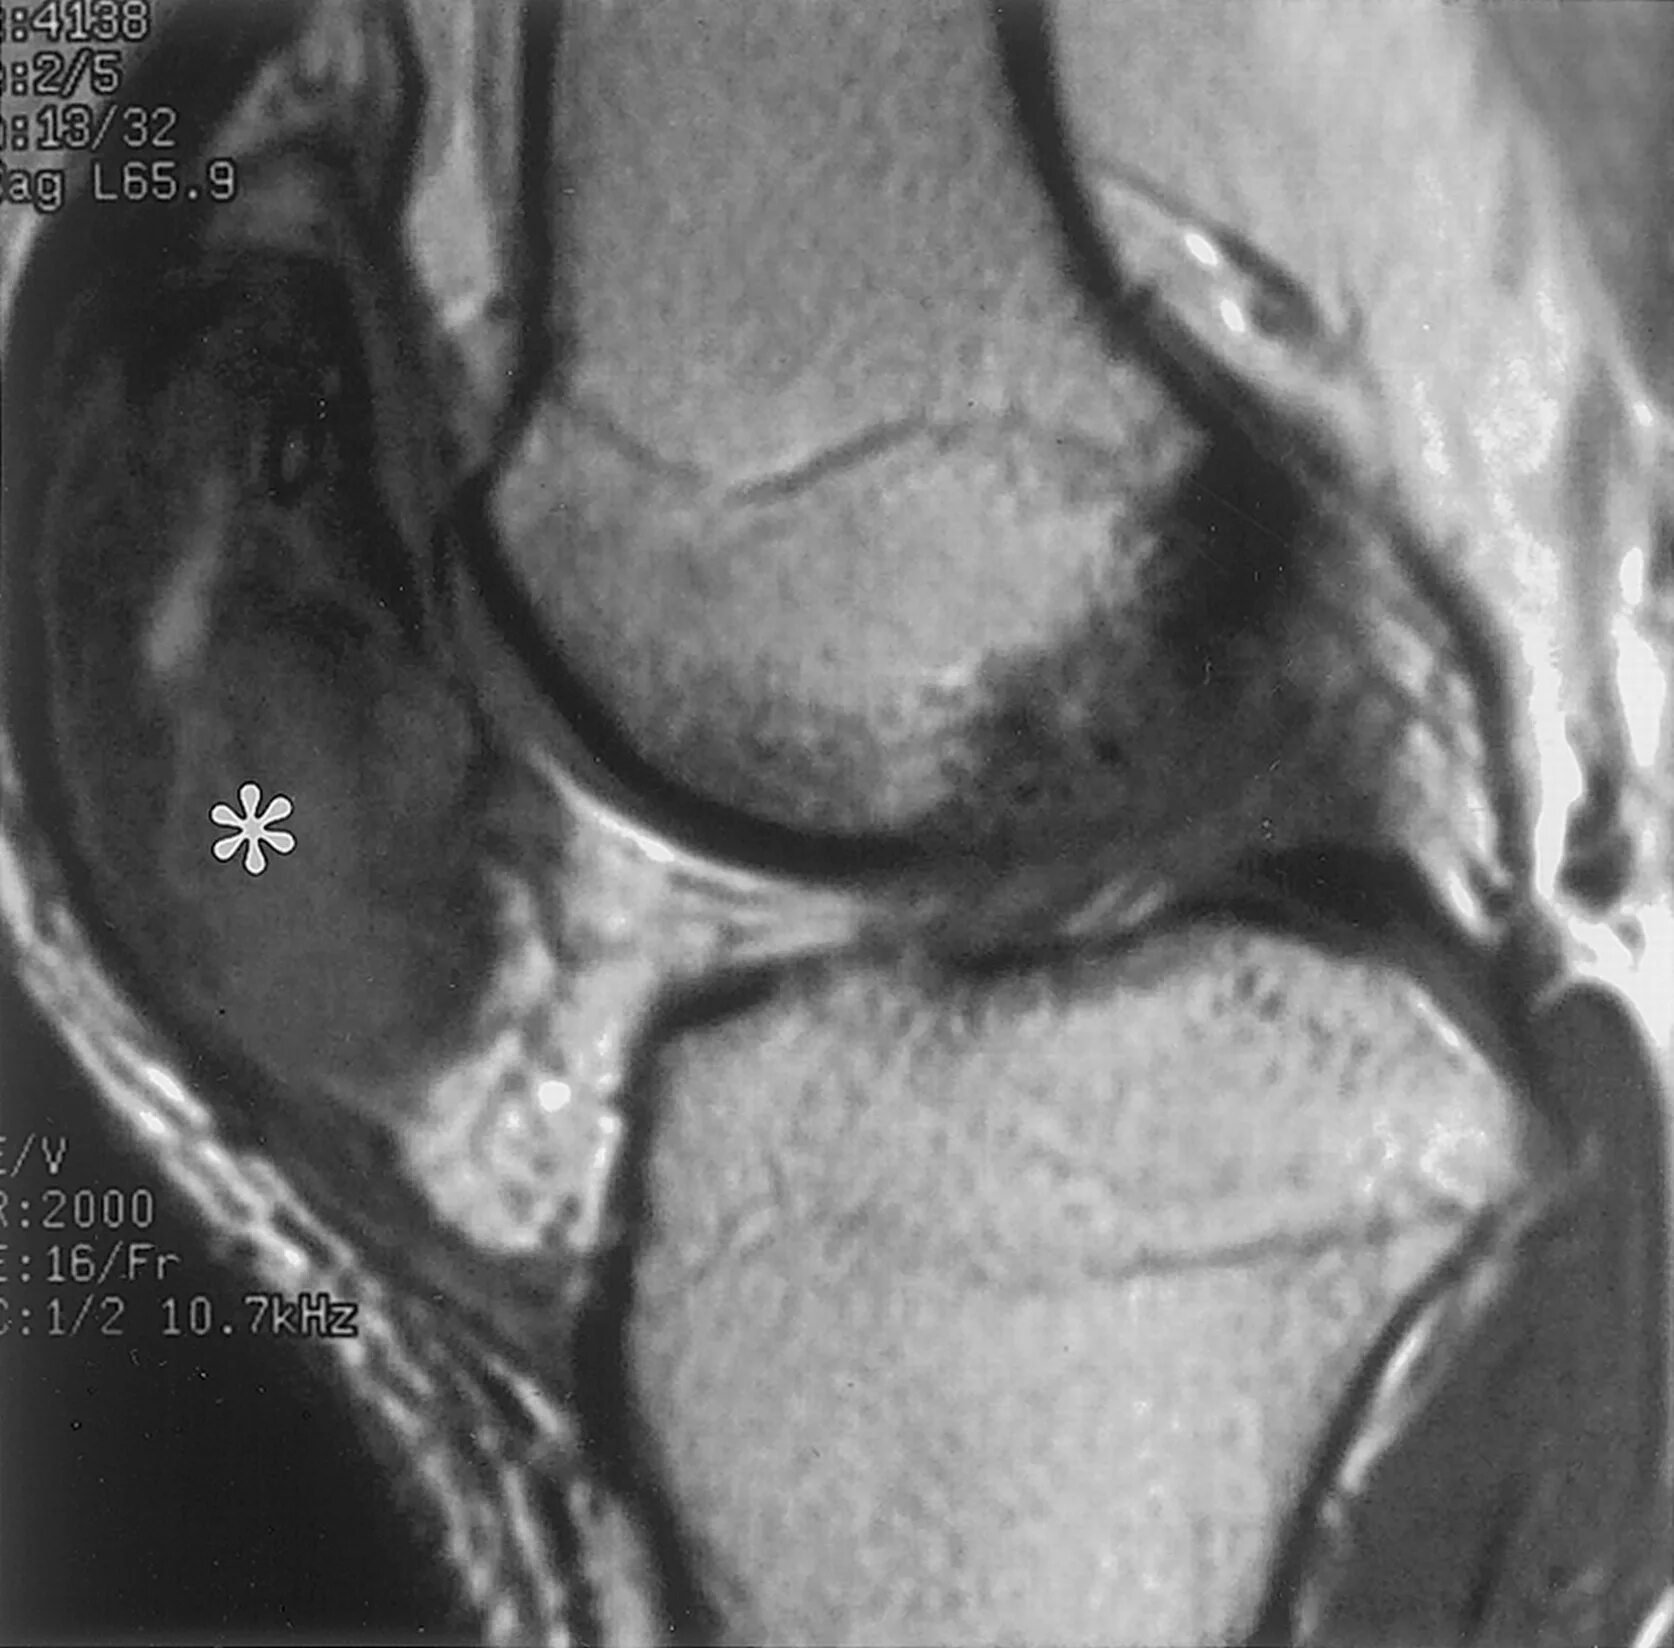

Синовиомы